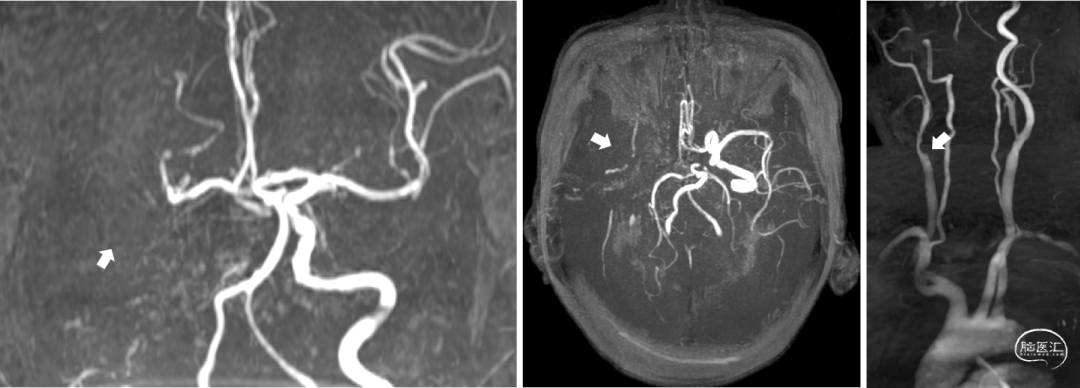

MRA:右侧大脑中动脉闭塞。

DWI:右侧额顶叶、岛叶、基底节区新鲜梗死病灶。

脑血管造影:3型主动脉弓,右侧颈内动脉起始段闭塞,后循环及左侧颈内动脉均未向左侧颈内动脉供血区代偿。

Cranial Cervical & Aortic arch MRA。

RICA C1闭塞,来自RACA丰富的软膜支代偿。